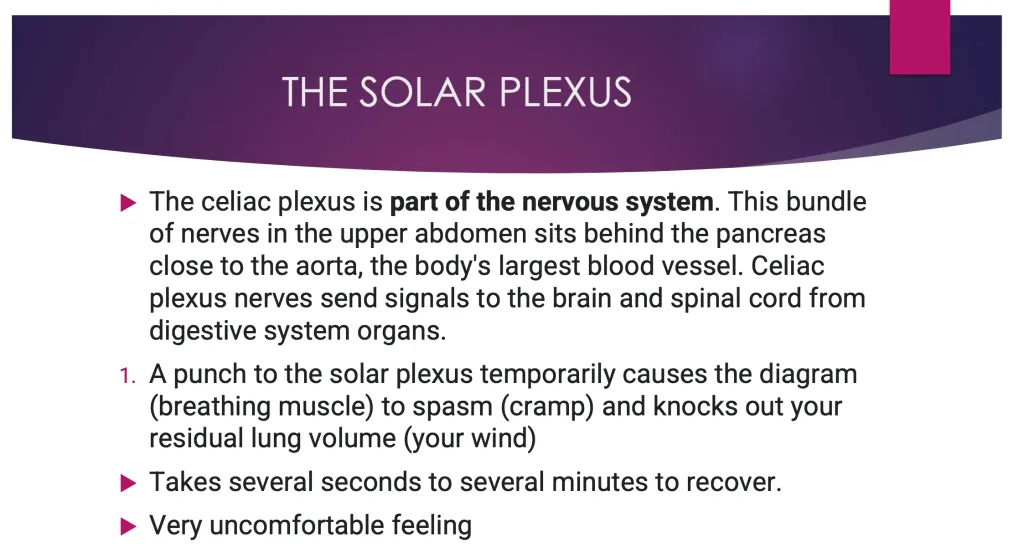

みぞおちへの衝撃は腹部中央に位置する腹腔神経叢(太陽神経叢)に影響を与えます。ここが刺激されてもどういうわけか横隔膜が痙攣を起こすようです(横隔膜の運動繊維は横隔神経(C4)であり、腹腔神経叢との関連がわからない…)。上のスライドは、Association of Boxing Commissions and Combative Sportsという機関のDr. Michael Schwartzとうい医師の作成したものですが、同様のことが記載されております。